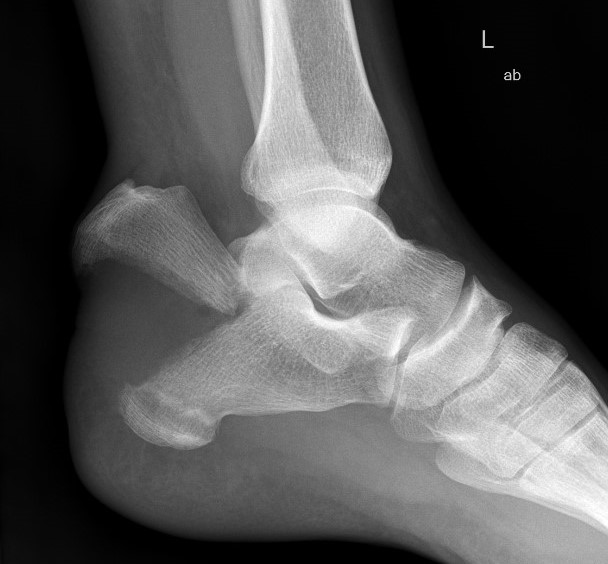

Anterior Process fracture

Anterior process

Attachment of bifurcate ligament

Part of complex sprain